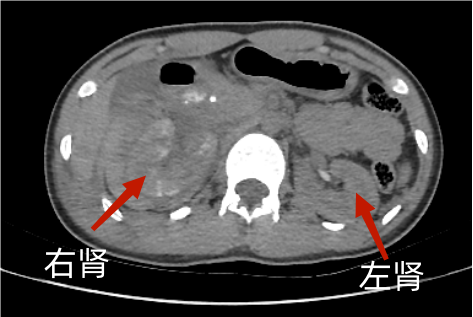

2024年12月6日,14岁的女孩小林(化名)因意外高空坠落被紧急送往我院阳逻院区急诊科救治。经急诊科医师初步诊断,小林右肾挫裂伤伴骨盆骨折、肋骨多发骨折、腰椎横突多发骨折。

泌尿外科主任占必兴、医师沈源清仔细研读患者CT影像资料,判断右肾损伤严重,需立即手术止血。传统的手术方式意味着要切除患者肾脏。患者的奶奶听闻可能要切除肾脏,眼泪止不住地往下流,她深知肾脏对年轻人意味着什么。奶奶哀求医生一定要保住孙女的肾脏。面对老人满含绝望与期盼的请求,占必兴深感责任重大,决定迎难而上,突破传统治疗的局限,探索更具人性化、既能止血又能保住肾脏的治疗新方案。

术前